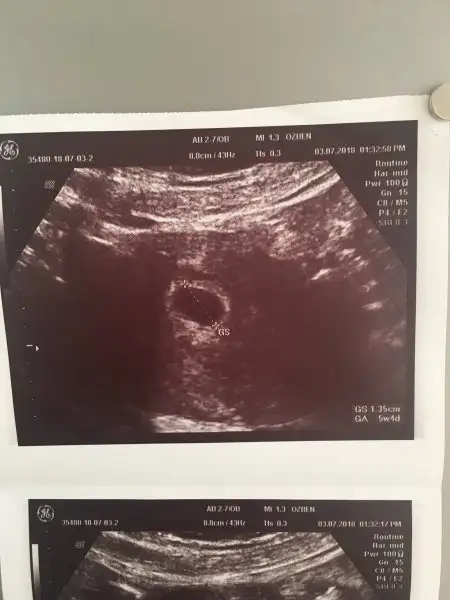

dün den beri düşünmeden duramıyorum acaba düşük mü yapacam 2 hafta geriden gelen ler bile bebeklerini kaybetmiş hep öyle yazıyor benim 4 hafta geri bugün 10 harfa 4 günlük olacaktıkyada yanlışmı ölçüm yapılıyor sizce 6+2 günlük bir kese ve bebek görünümü mü sizin demi bu hafta ki ultrasonlarınız böyle yoksa daha mı küçük içim içimi yiyo